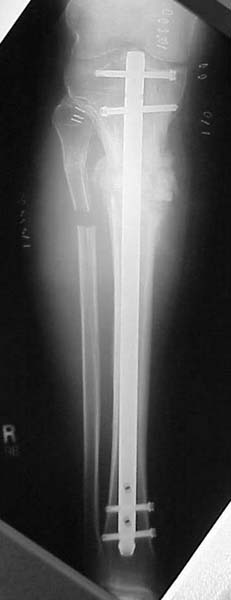

Thanks for the input on the tibia malunion w/ multiple plane deformity. I decided on a single cut osteotomy and IMN fixation based on desire to walk early, return to professor duties, and my previous experience w/ similar deformities (see another tibial malunion -below). The opening wedge was packed w/ a combination of autograft, allograft and demineralized bone.

Another tibial malunion -

Pt was 10 yrs s/p open tibia fx treated in a cast w/ IR, varus, 2 cm short, and recurvatum. He has done well post op.

18 mos postop